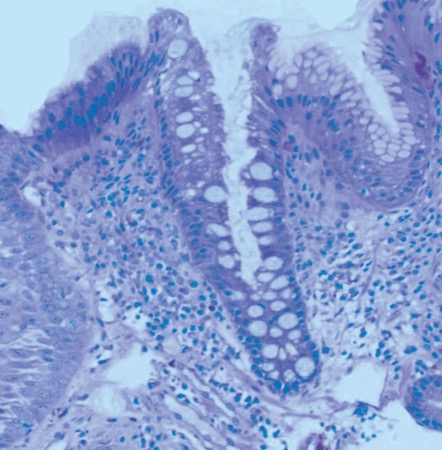

In response, Dr. Souza noted that the systems biology approach of the TSP-9 test evaluates multiple tissue layers, including epithelial cells, fibroblast and immune cells, as well as angiogenesis factors. In contrast, some clinical factors are subjective, such as the grade of dysplasia, and nonspecific, such as age. “If you think about it,” she said, “it’s really not surprising that these clinical factors actually detract from the accuracy of TissueCypher.”